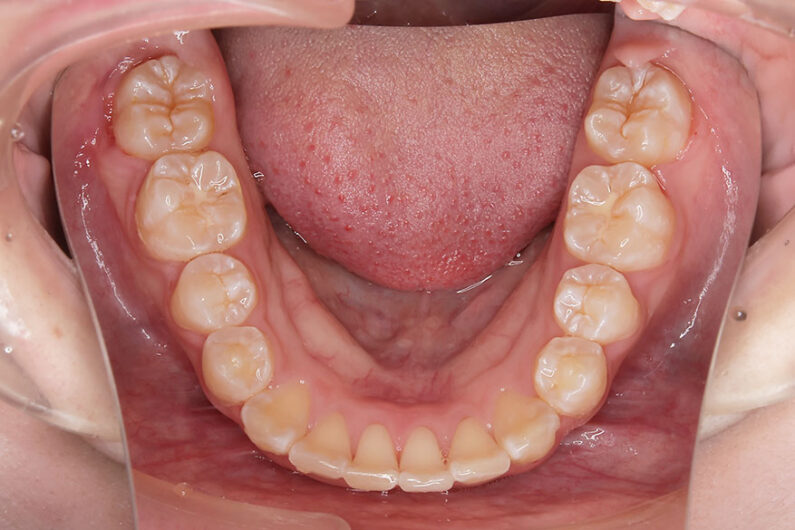

『前歯ががたついて生えてきた』 一般歯科から紹介の患者さんです。 上下4前歯に叢生がみられます。かみ合わせが深く、過蓋咬合。 上顎前歯は舌側傾斜。 永久歯の萌出スペースが上下とも5mmほど足りませんし、 おそらく、これから生えてくる犬歯は八重歯になる状況です。 治療方針としては、小児矯正で叢生(がたつき)を減らし、 永久歯列が生えてから、中学生ごろから本格矯正(マルチブラケット装置)を行います。 十分に側方拡大でスペースを確保し、更に、まだ生えていない永久歯の位置と方向が良ければ、きれいに生えそろうことにより、本格矯正での治療が必要ない場合もありますが頻度的には少ないです。 ある程度はきれいに生えてきても、左右の歯の高さの違いや、歯の回転、角度のズレが残る場合が多いからです。 その多少のがたつきが気にならないのでしたら、小児矯正で終了です。

小児矯正での早期治療で、側方拡大による十分なスペース確保をしていたことと、口唇の前突傾向がなかったことから、